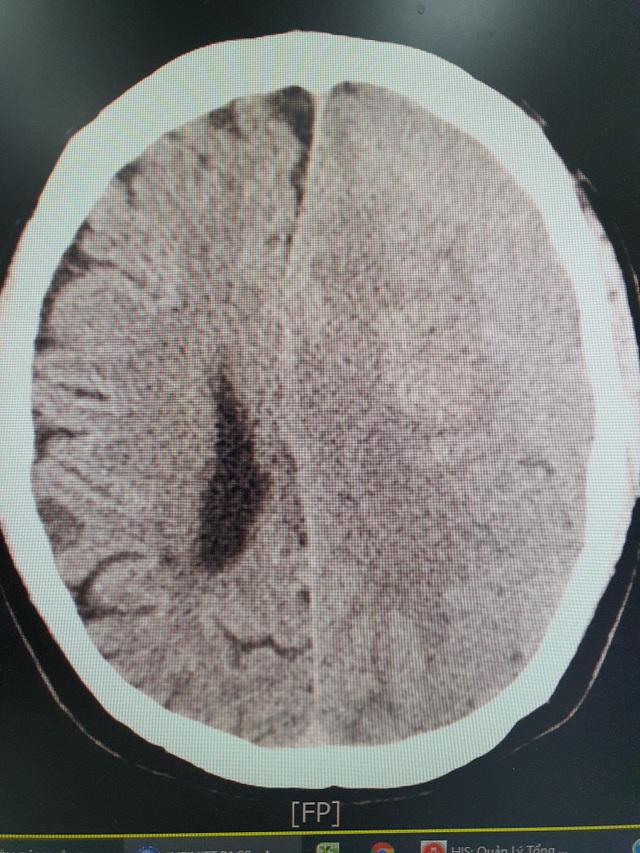

Khối xuất huyết não của bệnh nhân trên hình ảnh chụp CT.

BS Khiêm cho biết, khi tiếp nhận bệnh nhân, các bác sĩ đã nhanh chóng chỉ định chụp cắt lớp CT và phát hiện bệnh nhân bị xuất huyết não có cục máu tụ dưới màng cứng. Ngay lập tức, bệnh nhân được tiến hành xử lý lấy máu tụ và sức khoẻ ổn định sau 4 ngày can thiệp.